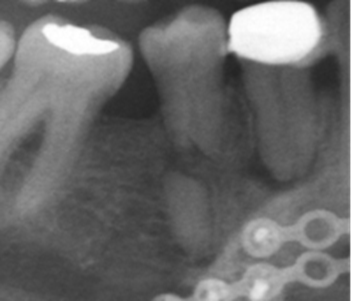

Los resultados mostraron que en el 48 % de la población se encontró algún hallazgo relacionado con la pulpa dental, con frecuencias similares entre hombres y mujeres, siendo el tratamiento endodóntico el más frecuentemente encontrado (Tabla 1, Fig. 1). El rango del número de endodoncias por radiografía fue de 1 a 18. El 86,4 % de las radiografías presentaron de 1-5 endodoncias, 11,4 % de 6-10 y el 2,2 % de 11-18. La presencia de zona radiolúcida periapical seguida por la reabsorción (Fig. 2), fueron los siguientes hallazgos más frecuentes. (Tabla 1)

El análisis de la presencia de zona radiolúcida periapical, mostró que del total de dientes en boca, el 0,6 % de los que no tenían endodoncia tienen lesiones apicales mientras que el 11% de los que tienen endodoncia se asocian con una lesión apical (p<0,000000). Sin embargo el cálculo del OR (OR=0,047) mostró una relación negativa de riesgo entre tener una endodoncia y presentar lesión apical. De los 389 dientes en los que se observó el hallazgo compatible con radiolucidez periapical, 171 (44 %) tenían tratamiento endodóntico, de los cuales 66 % estaban subobturados, 31% bien obturados y 3% sobreobturados.

Del total de dientes estudiados, el 0.97 % en el 18,3 % de las radiografías, tiene asociada una lesión apical con tendencia a disminuir con la edad, a diferencia de otros reportes en los cuales pasa de una prevalencia del 50 % a los 50 años a una de 62 % a los 60 años y más8 o en Brasil con una prevalencia de lesiones del 7,87 %,9) lo que se explicaría aquí porque los pacientes prefieren la exodoncia a los retratamientos o las cirugías apicales. La presencia de lesiones apicales indica mayores necesidades de tratamiento puesto que se necesita rehacer la endodoncia o cirugías apicales, que pueden dar pronósticos desfavorables al diente tratado y aumentar los costos.

Un hallazgo importante en este estudio fue encontrar que el 52,7 % de los dientes se consideraron subobturados, asociados en un 66% con lesiones apicales vs el 44.9 % en aquellos que estaban en límites de normalidad. Esto coincidiendo con De Moor y colaboradores 11 que encuentran que del 6,8 % de dientes que están obturados, el 56,6 % fueron considerados mal obturados. Un análisis utilizando tomografía de rayo de cono, mostró que el 23,04 % de dientes están mal obturados y en ellos el riesgo de tener una lesión apical aumenta en 4,38 veces17. Un estudio de Moreno y colaboradores18 mostró que el 51% de los dientes tratados, no presentaban patologías perirradiculares y solo el 33% se consideraron correctamente obturados.

La presencia de hallazgos compatibles con reabsorción externa se observó en 27 radiografías con alta variación entre género y edad. Se sabe que la reabsorción externa ha sido relacionada con varios factores, pero gran parte se debe a tratamientos ortodónticos siendo una condición irreversible y que afecta negativamente el pronóstico de los dientes19.